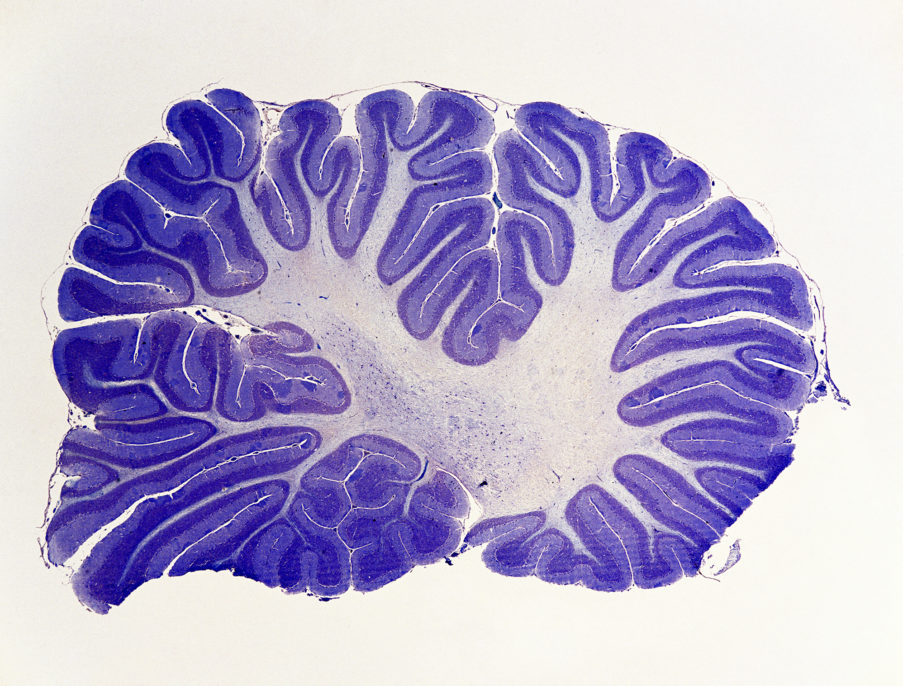

An ancient part of the brain long ignored by the scientific world appears to play a critical role in everything from language and emotions to daily planning.

It’s the cerebellum, which is found in fish and lizards as well as people.

But in the human brain, this structure is wired to areas involved in higher-order thinking, a team led by researchers from Washington University in St. Louis reports Thursday in the journal Neuron.

This allowed the team to quantify the various connections between the cerebellum and other brain areas. And what they found was that just 20 percent of the cerebellum was dedicated to areas involved in physical motion, while 80 percent was dedicated to areas involved in functions such as abstract thinking, planning, emotion, memory and language.

“What’s happened over time is that the cerebellum has expanded enormously,” he says. And this extra capacity has allowed it to take on functions beyond motion.